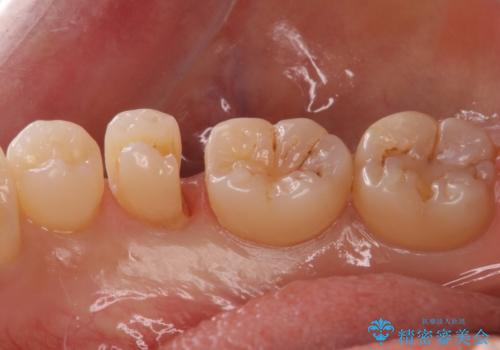

歯と歯の間の虫歯 セラミックインレーでの修復処置

- 検査の結果、歯と歯の間に虫歯が確認された患者様です。

虫歯を除去した後、セラミックインレーで修復処置を行います。

- 右下5 セラミックインレー 77,000円費用は治療当時の料金となります

レントゲン画像では写りにくい小さな虫歯も発見したため、そこも含めた形での修復処置を行いました。